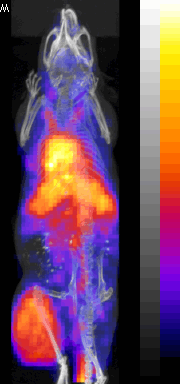

PET/CT Images

Nude mouse with a SUM190 tumor received intravenous antisense (anti-RIa)

18F-MORF/tat/Herceptin nanoparticle and PET/CT images obtained at at 3 and 8 hr.